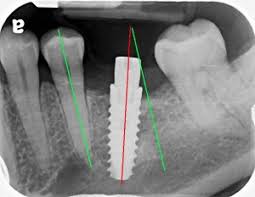

경사 식립은 수직 식립보다 훨씬 정밀한 사전 계획이 필요합니다.

기울기가 조금만 어긋나도 보철물 제작이 어려워지거나,

교합력이 임플란트 나사에 비스듬하게 전달돼 장기적으로 합병증으로 이어질 수 있습니다.

저는 경사 식립 케이스에서 반드시 CT 기반 3D 시뮬레이션을 선행합니다.

임플란트의 장축 방향, 보철물 수직 공간, 인접 구조물과의 안전 거리를

입체적으로 계산한 뒤, 서지컬 가이드를 활용해

계획된 각도를 수술실에서 정확히 구현합니다.

‘감’이 아니라 계획이 먼저입니다.